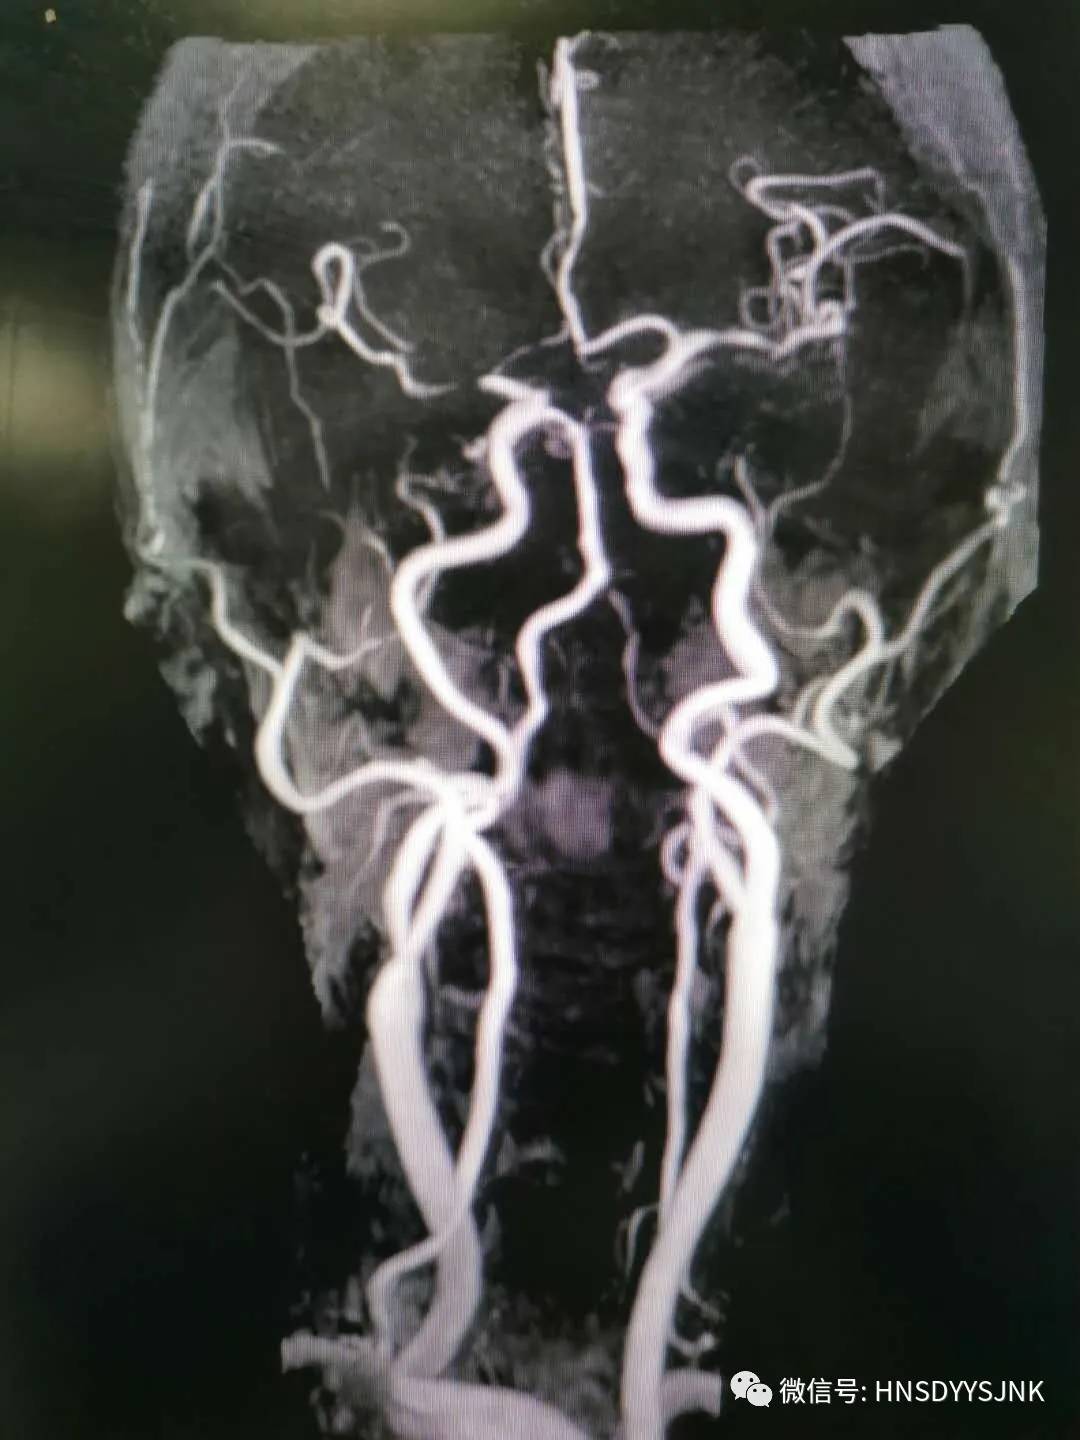

2月28日,急诊科电话通知神经内科,有卒中病人可能需要静脉溶栓。原来是一位72岁的老人,她突发右侧肢体无力,急诊科医生快速评估后,考虑急性脑卒中,立即启动卒中绿色通道。

为了杜绝新冠肺炎的交叉感染,急诊科医师和神经内科医师一起快速核查排,并除新冠病毒感染后,在科室副主任指导下,神经内科医护人员有条不紊的做好静脉溶栓工作。严密紧张地监测患者生命体征、溶栓效果及是否出现并发症,溶栓进行半小时后,患者右侧肢体肌力恢复正常,家属对溶栓效果满意。

时间就是大脑,一分钟延误,可能导致患者肢体功能残疾,影响今后的生活质量。脑梗死溶栓必须争分夺秒,而新冠肺炎防控也不容马虎。自1月下旬以来,在急诊科、神经内科、放射科、神经外科、介入科、检验科等医院卒中团队相关科室的积极协作下,已经开展静脉溶栓10余例,为卒中患者提供了高效优质的服务。